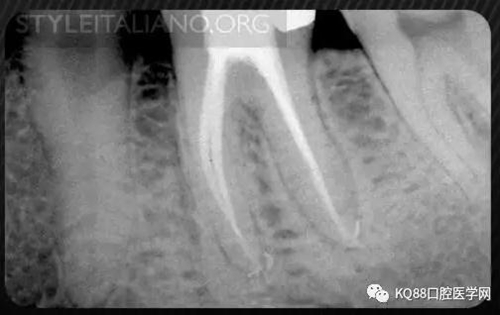

Case 1: In this patient, persistent pain was present after endodontic treatment of a vital tooth. The periapical x-ray showed an inadequate shaping of the distal root canal, regarding both the working length and the apical taper.

Img. 2 - Retreatment of distal canal was performed using ProTaper retreatment files. Working length was assessed electronically. Canal was shaped with a Reciproc R40, thoroughly irrigated with US activation, filled with corresponding Guttafusion obturator. Pain disappeared completely some days after retreatment. In all likelihood, incomplete preparation allowed residual pulp tissue to remain in the root canal, acting as an irritant.